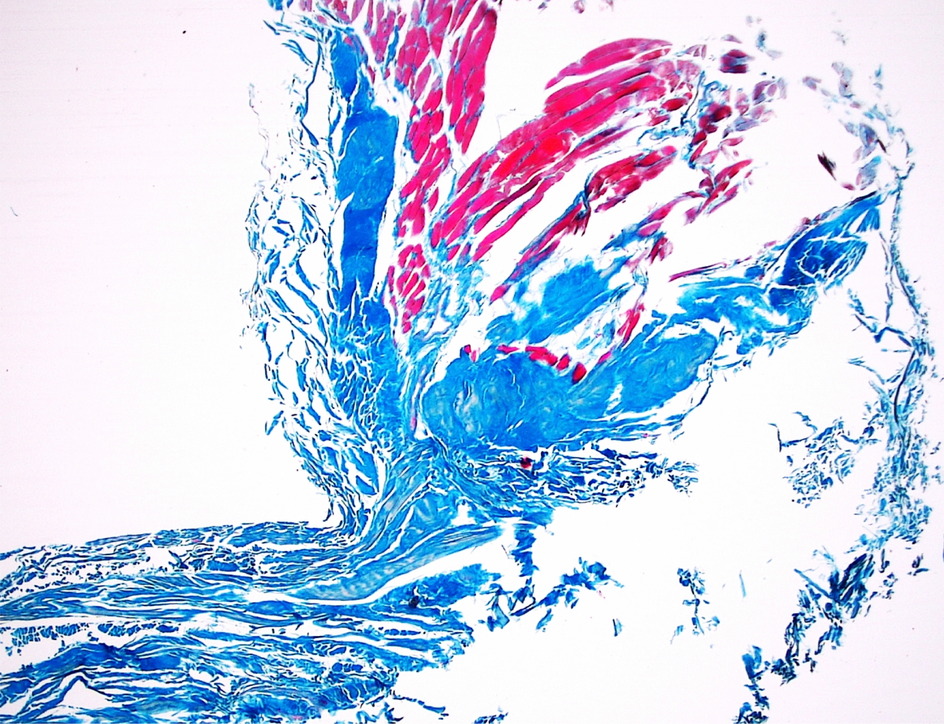

Figure 6

Histological examination of the aponeurosis of the popliteus muscle—2 × magnification. The Fig. 6 was taken with Olympus EP50 camera (Olympus Corporation Japan).